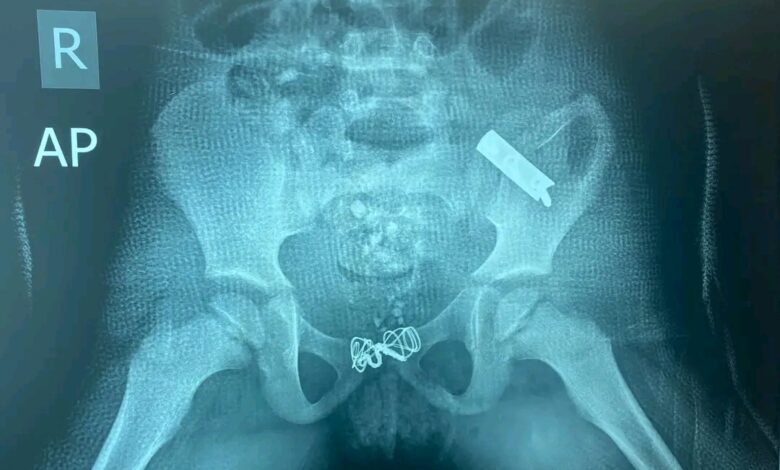

تمكن فريق من شعبة جراحة العظام و الكسور في مستشفى  الشهيد غازي الحريري بمدينة الطب من معالجة حالة معقدة لطفل يبلغ من العمر خمس سنوات، أصيب بكسر غير مستقر في الحوض نتيجة لحادث سير شديد و قد أظهرت الفحوصات وجود كسر مع إنحراف و هجرة للنصف الأيسر من الحوض نحو الأعلى ما أستدعى تدخلاً جراحياً طارئاً لإعادة المفصل و الهيكل العظمي إلى وضعه الطبيعي و تثبيته بواسطة التثبيت الداخلي، و قد تكللت العملية بالنجاح حيث إستعاد الحوض وضعه التشريحي المناسب مع إستقرار جيد بعد التثبيت، و تألف الفريق الجراحي من الدكتور لواء فاضل طالب إختصاصي جراحة العظام و الكسور (رئيس الفريق) و الدكتور ليث سالم طالب دراسات بورد عراقي و الدكتور أحمد عدي طالب دراسات بورد عربي و الدكتور منتظر علي و فريق التخدير الدكتور مهند عبد الكريم إختصاصي تخدير و الملاك التمريضي.